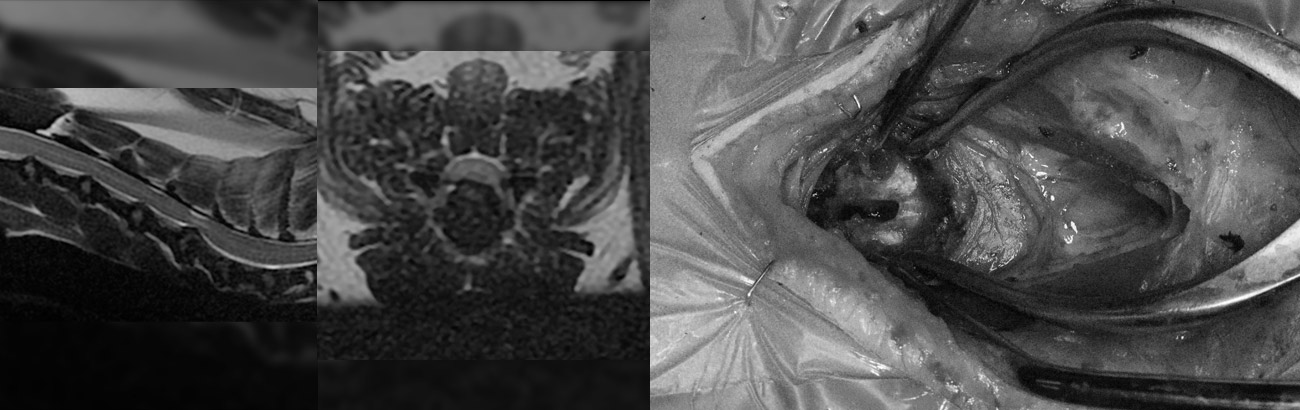

• 예시이미지

경추 디스크 수술 (Ventral slot)

예시이미지

- T12-13 수준의 척수 배쪽으로 T1 저신호. T2 저신호 물질 : IVDD (extrusion)

: 디스크 물질은 중앙 - 좌측에 치우쳐져 있으며, 30% 가량 척수압박(), 디스크 물질은 후방 T13 추체 수준까지 이어짐

: 디스크 물질의 T2* 저신호 (epidural hemorrhage, ) 및 수막/ 디스크 물질의 조영증강()

흉요추 디스크 수술 (Hemilamiectomy)